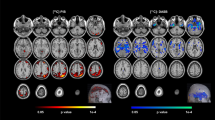

This study was conducted to clarify patterns of cortico-limbic volume abnormalities in late life depression (LLD) relative to non-depressed (ND) adults matched for amyloid β (Aβ) deposition and to evaluate the relationship of volume abnormalities with cognitive performance. Participants included 116 LLD and 226 ND. Classification accuracy of LLD status was estimated using area under the receiver operator characteristic curve. Twenty-one percent of LLD and ND participants were Aβ positive and the groups did not differ on white matter hyperintensity volume (WMH (logscale); β = 0.12, p = 0.28). Compared to ND, the LLD group exhibited significantly lower bilateral volume in the lateral orbitofrontal cortex, hippocampus, accumbens area, superior temporal lobe, temporal pole, and amygdala after multiple comparison correction (p < 0.009 for all). Cortico-limbic volumes significantly improved classification of LLD beyond demographic characteristics, Aβ status, and WMH (AUCVol = 0.71, AUCWMH, Aβ = 0.62, AUC difference, 0.09 [0.03 to 0.15]). LLD exhibited poorer performance on measures of global cognition, set shifting, and verbal learning and memory relative to ND. Cognitive function was positively associated with cortico-limbic volumes and these relationships did not differ by group. Secondary analyses with an ND sample additionally matched for Mild Cognitive Impairment (MCI) diagnosis showed a similar but attenuated pattern of volume abnormalities. Overall, our results support LLD as being associated with cortico-limbic volume abnormalities that are distinct from Aβ and white matter pathologies and that these volume abnormalities are important factors associated with cognitive dysfunction in LLD.